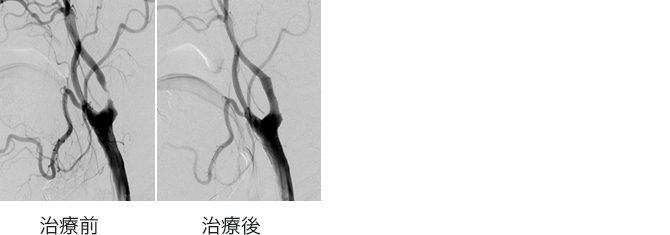

頸動脈狭窄症に対するステント留置術

首の血管が細くなったために脳梗塞を起こした場合や、今後脳梗塞を起こす危険が高い場合に血管を広げるためのステント留置術を行います。局所麻酔でほとんどの治療は可能ですが、病変によっては全身麻酔で行うこともあります。治療後に血圧が下がり脈拍が遅くなることがありますので、循環器内科と連携して安全に治療できるよう努めております。